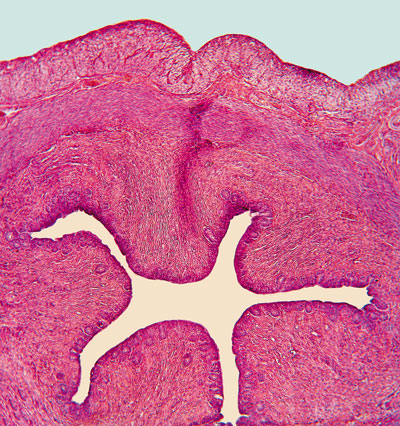

Мал. 13. стократно збільшення поперечного зрізу уретри

Останніми з елементів, що виявляються при організованою гематурії, є циліндри. Вони являють собою білки, які згорнулися в просвіті ниркових канальців і включають в свій склад будь-який вміст просвіту канальців. Особливістю циліндрів є їх здатність набувати форму самих канальців. У нормі в загальному аналізі сечі циліндри не виявляються. Поява ж циліндрів в сечі говорить про патологію нирок, а їх вигляд особливого діагностичного значення не несе.